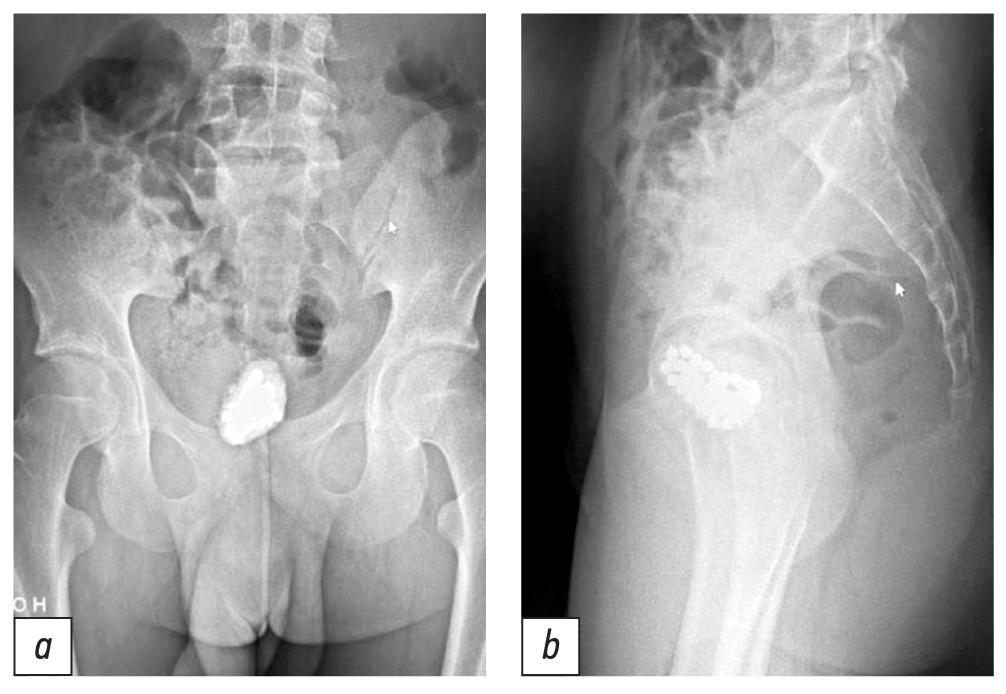

Ребёнку была выполнена рентгенография органов таза: в прямой и боковой проекции мочевого пузыря определяются множественные тени инородных тел, окружённые оссификатом, общим размером 46×30×34 мм (рис. 1, 2).

Рис. 1. Инородные тела мочевого пузыря на обзорной рентгенограмме органов малого таза: a — прямая проекция, b — боковая проекция.

Fig. 1. Foreign bodies of the bladder on a plain radiograph of the pelvic organs: a — frontal projection, b — lateral projection.